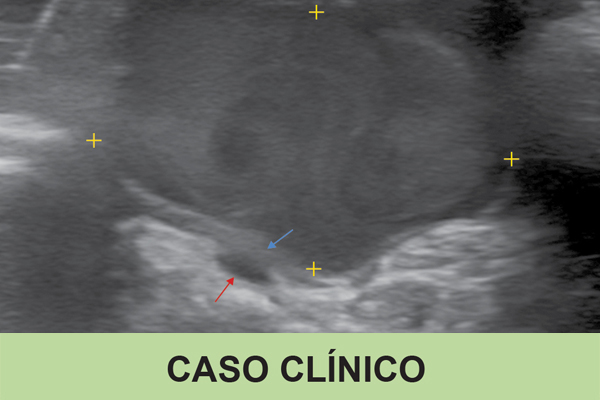

Species associated with visceral leishmaniasis, such as L. infantum, may be responsible for cutaneous leishmaniasis (CL), particu...